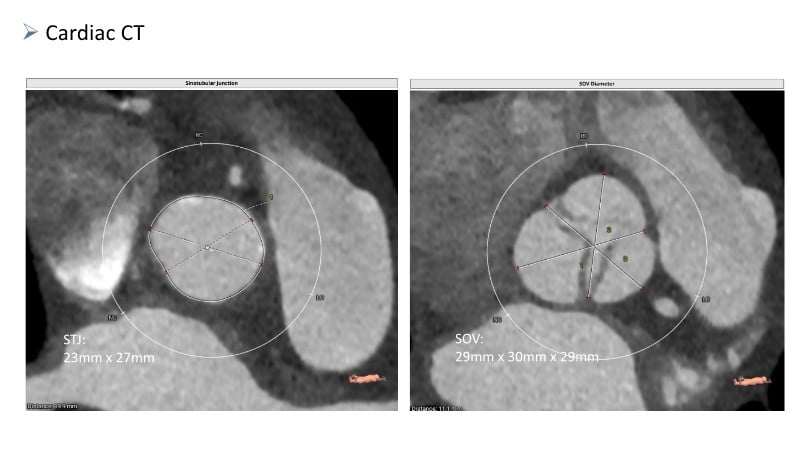

Discover how thoughtful index valve selection and implantation techniques can shape the long-term management of patients undergoing TAVI. This PCR London Valves 2025 session highlights treatment considerations for low- and intermediate-risk patients, explores how valve choice affects the feasibility of future interventions, and examines strategies to achieve optimal and durable clinical outcomes. Follow real patient case with imaging analysis, hemodynamic insights in small annuli, and discussions on planning for future revalving and coronary access.